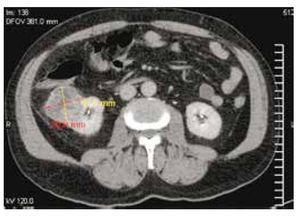

Cuenta como antecedente de importancia: hipertensión de 15 años de evolución en tratamiento con enalapril una tableta cada 8 horas, además de exposición crónica a productos del antimonio inhalado por su trabajo como soldador ahora ya pensionado, como factores de riesgo6,7, niega alguna otra enfermedad crónica, pérdida de peso ponderal o síntomas constitucionales, refiere nunca haber fumado. Se realiza entonces tomografía computada (TC) abdominopélvica simple y contrastada, encontrando tumor renal heterogéneo de 50 x 45.9 mm, invadiendo desde cáliz medio hasta espacio cortical, la cual tiene realce periférico de medio de contraste (figs. 2 y 3), sin evidencia de metástasis torácica o local, vejiga sin lesiones ocupantes. Se realiza además pruebas de laboratorio complementaria reportando Hb: 12.6 g, Hto: 35.6%, plaquetas: 142,000, leucos: 8.4, glucosa: 120 mg, urea: 53 mg, creatinina: 1.04 mg, tiempos de sangrado y pruebas funcionales hepáticas dentro de parámetros normales. Uroanálisis: leucocitos 0 por campo, eritrocitos 0 por campo, bacterias proteínas y nitritos negativo.

Figura 2. Corte topográfico donde se muestra una lesión sólida de 4.5 x 5.0 cm, en su borde externo del riñón derecho con densidad heterogéneo.